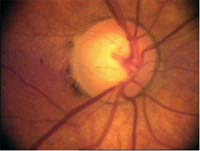

Tento terč má širokou cirkulární peripapilární atrofii, která opticky vytváří falešný dojem širokého neuroretinálního lemu, zvláště nasálně.